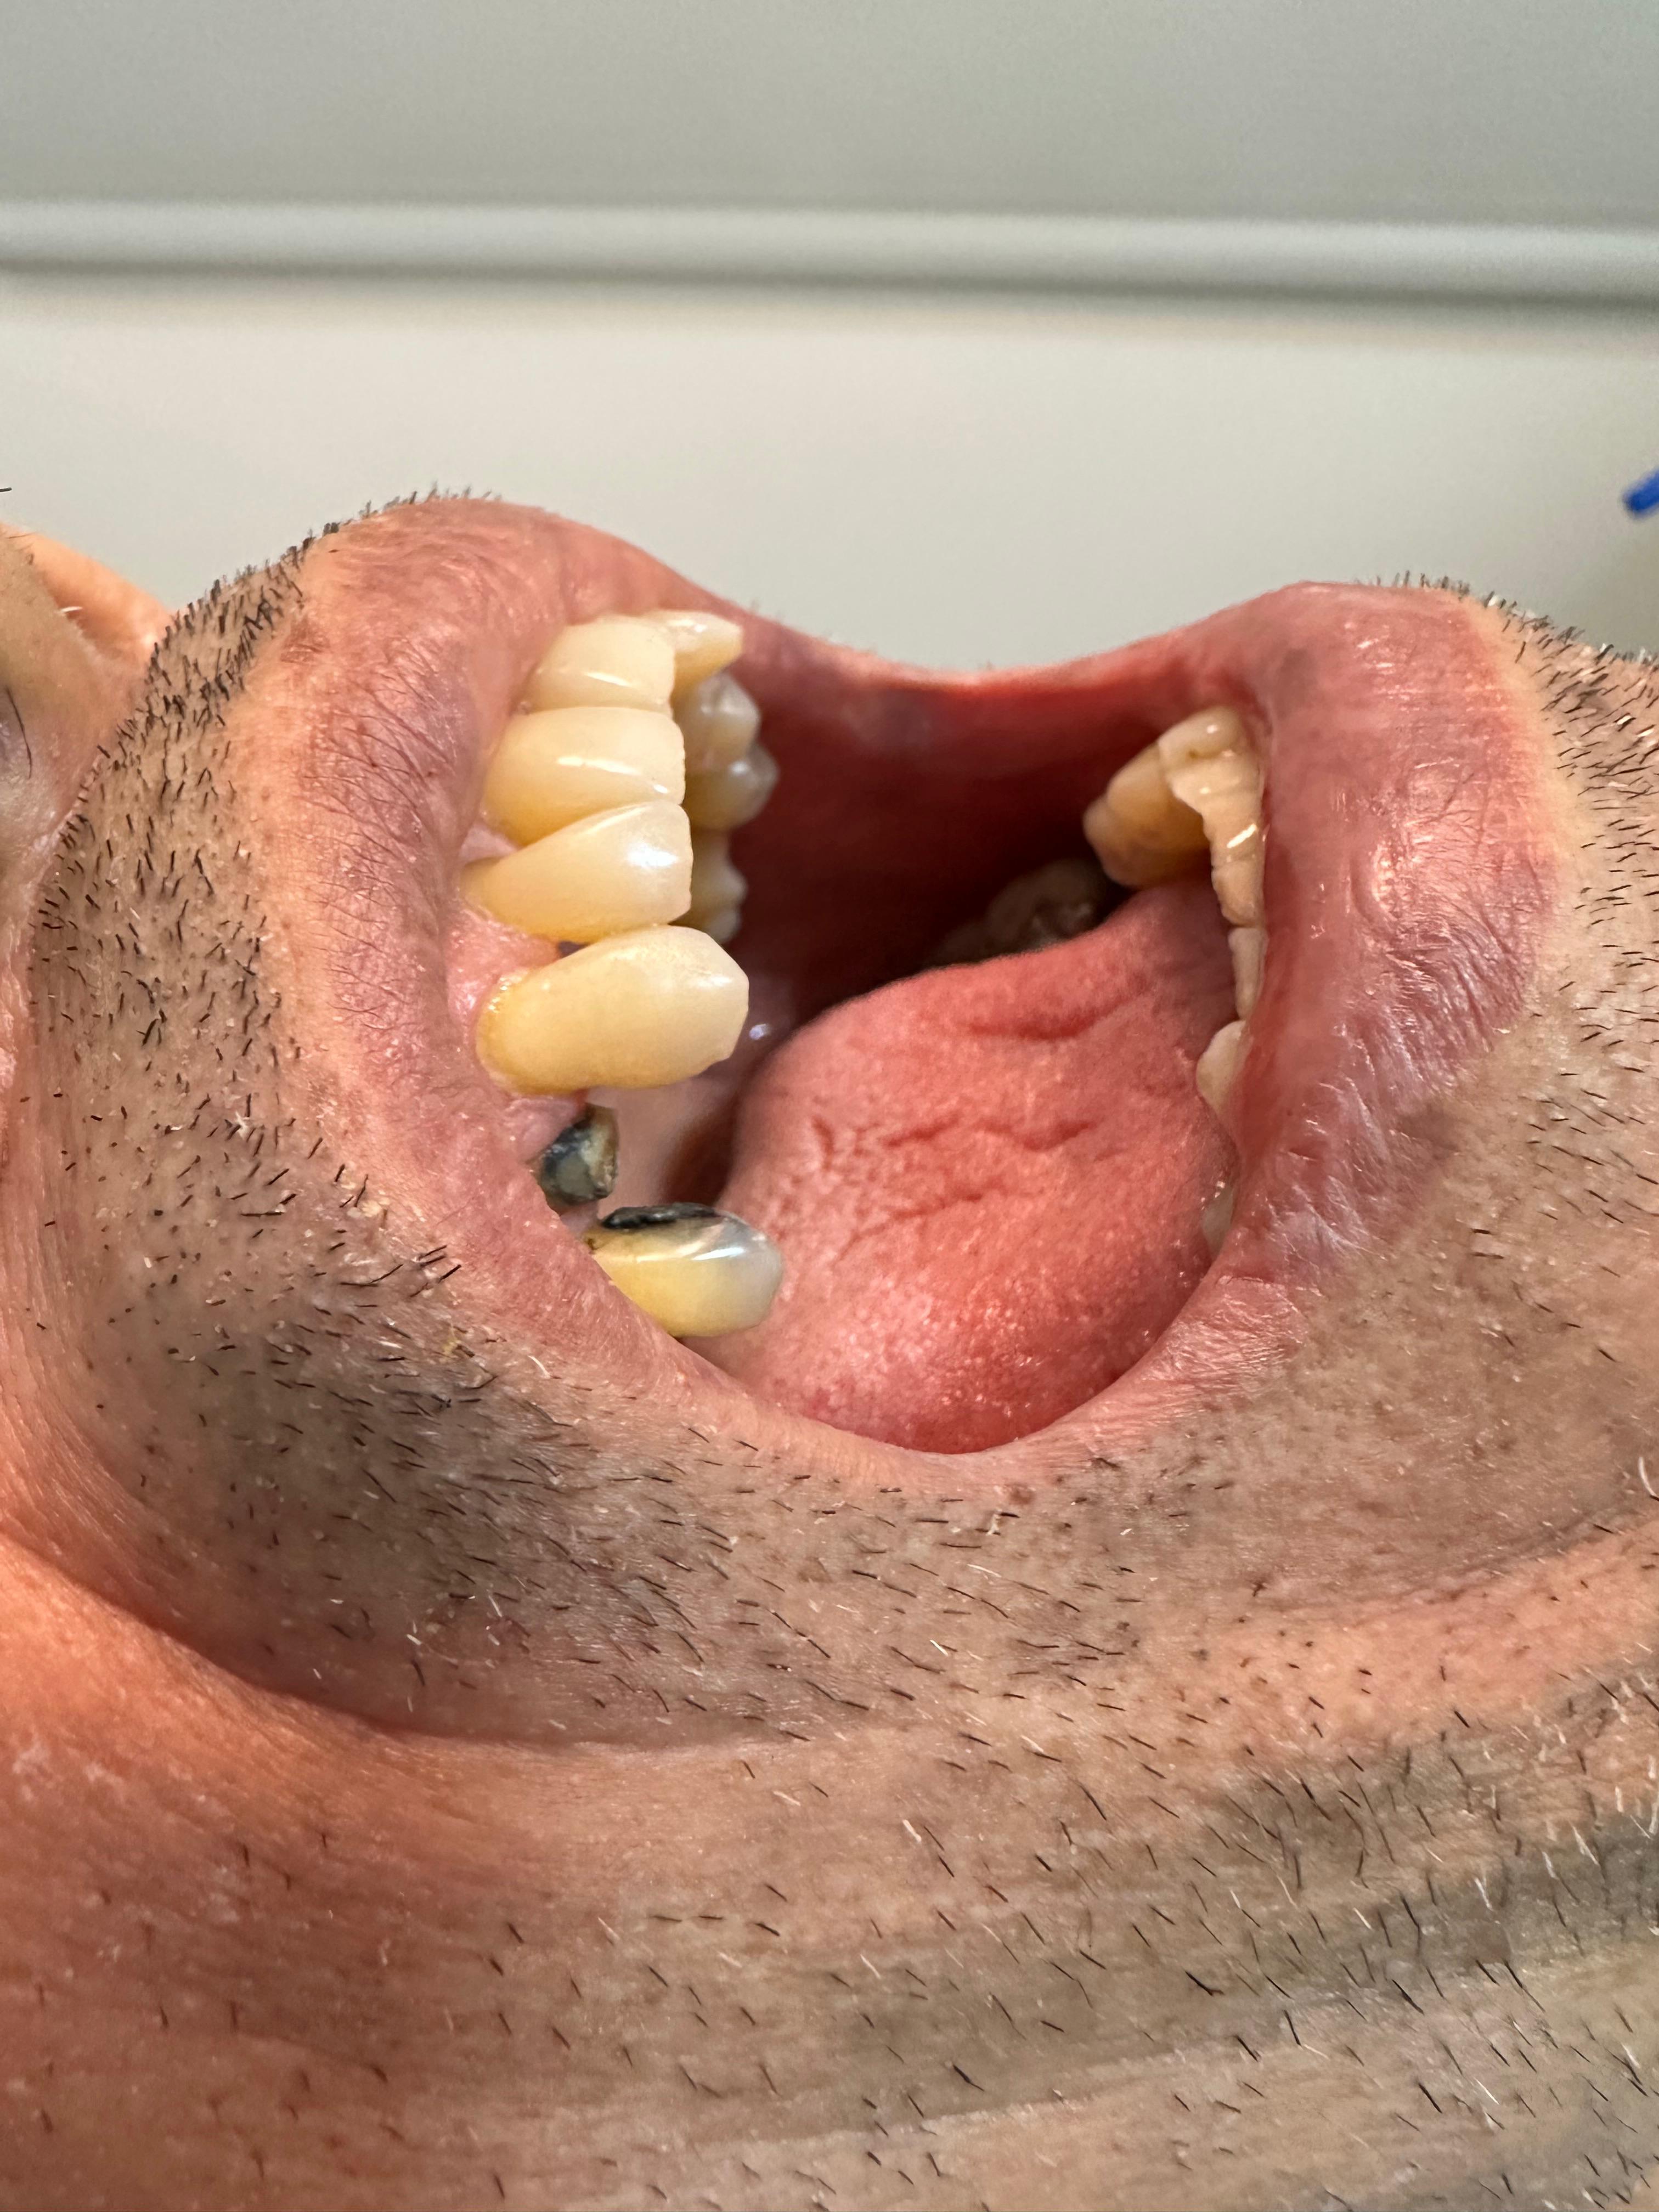

Una radiografía periapical es un tipo de imagen dental que muestra en detalle uno o dos dientes completos, desde la corona hasta la raíz y el hueso circundante. Se utiliza comúnmente para:

• Detectar caries dentales debajo de las encías.

• Observar la salud del hueso que sostiene el diente.

• Diagnosticar abscesos, infecciones o quistes.

• Evaluar el estado de los tratamientos de conducto.

• Examinar dientes fracturados o con problemas periodontales.